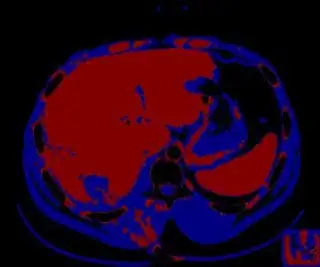

Below I apply two successive morphological openings to the image using a 3x3 circular kernel, and then apply k-means clustering to the gray levels. From your sample images and some I found on the internet, I decided to set k = 4. If you are using high-resolution images, first downsample them to dimensions ~400-600. Otherwise the morphological operation may not have a significant effect, and the k-means will be slow.

Below are some of the opened and segmented images. Of course there's more to be done in terms of

- separating out the liver region

- generalizing this to a large dataset

but hope this is at least a starting point.

You might be able to narrow down the region or interest by filtering out the darkest and the lightest regions from the segmented image. For this, use the k-means cluster centers, check for the extreme values (max and min) and remove the corresponding k values from the labeled image. Then you can look for large structures to the left of the result image. Worst case, you might get a hole on the left side when the extreme region filtering goes wrong. I've updated the code and results.